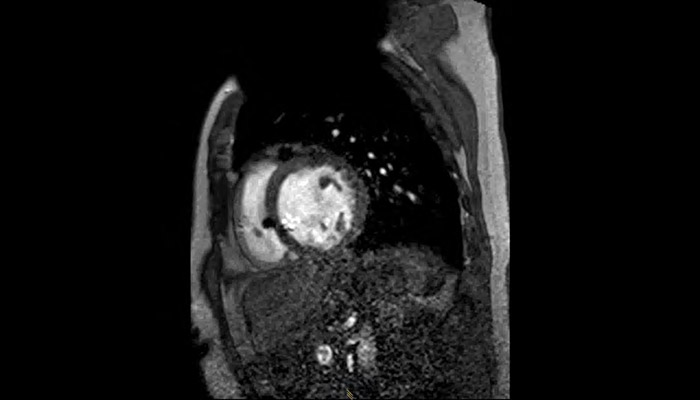

A patient with an MR Conditional ICD and suspected myocarditis presented for MRI. This short axis view of the heart is created with an SSFP (steady state free precession) sequence on a Philips Achieva 1.5T system. The cardiac MRI exam reveals normal dimensions and regular function of the right and left ventricle. Note the ICD lead in the right ventricle (arrow) and the signal void in the left pectoral region, indicating the ICD-IPG (asterisk). Courtesy of Dr. Sommer.